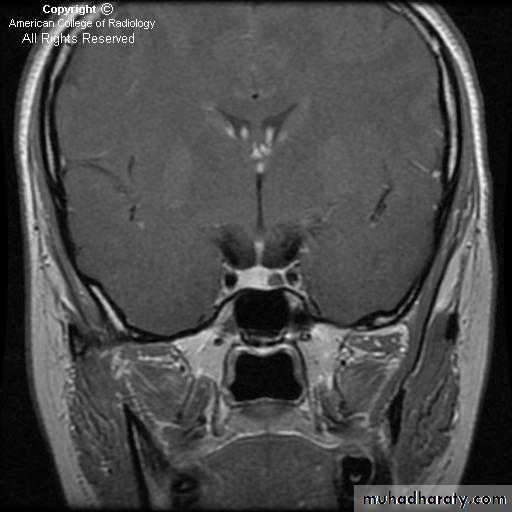

MRI is the investigation of choice for imaging of the pituitary gland and adjacent structures.

• Sagittal T1-weighted images demonstrate the lobar anatomy of the pituitary:

• Adenohypophysis of similar signal intensity to brain tissue

• Neurohypophysis seen as a posterior ‘bright spot’.

• Coronal T1-weighted scans with dynamic contrast enhancement are particularly useful for the diagnosis of microadenomas. Where MRI is unavailable or contraindicated CT may be used, however it is much less sensitive.